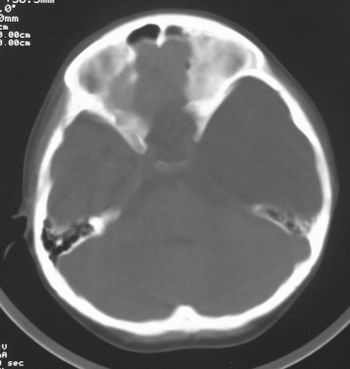

患儿,男,8岁,外伤2小时,无恶心、呕吐,四肢活动正常。既往无任何不适,智力发育正常。

典型的左中颅窝蛛网膜囊肿。

左侧中颅窝蛛网膜囊肿

左颅中窝蛛网膜囊肿。

典型的左中颅窝蛛网膜囊肿。最常见的发病部位,张力比较高,相应颅板受压变薄。赶紧治疗,脑组织的功能可能部分恢复。